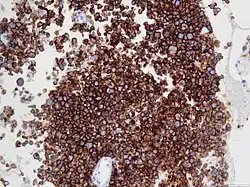

ALCL is defined based on microscopic histopathological examination of involved tissues which shows the presence of at least some ALCL-defining pleomorphic cells. These "hallmark" cells have abnormal kidney-shaped or horseshoe-shaped nuclei, prominent Golgi, and express the CD30 tumor marker protein on their surface membranes.[4] In 2016, the World Health Organization (WHO) separated ALCL into four types: ALK-positive ALCL (also termed ALK+ ALCL), ALK-negative ALCL (ALK− ALCL), primary cutaneous ALCL (pcALCL), and breast implant-associated ALCL (BIA-ALCL). WHO defined BIA-ALCL as an ALCL type provisionally, i.e. subject to redefinition if future studies should support such a change.[4][5]

ALK-positive ALCL is diagnosed by histological and immunological examinations of involved tissues, typically lymph nodes. These tissues have lymphoma-like infiltrates that have variable numbers of ALCL "hallmark" cells, i.e. cells with kidney- or horseshoe-shaped nuclei that strongly express CD30 as detected by immunohistochemistry and an ALK fusion protein as detected by fluorescence in situ hybridization.[11] These cells are scattered throughout the infiltrates. WHO classifies these infiltrates into 5 patterns: a common pattern consisting of large variably shaped cells with large nuclei that typically contain multiple nucleoli (60–70% of cases); a small-cell pattern consisting of small to medium-sized neoplastic cells with clear cytoplasm and "hallmark" cells that are concentrated around small blood vessels (5–10% of cases); a lymphohistiocytic pattern consisting of small neoplastic cells along with abundant histiocytes (10% of cases); a Hodgkin's-like pattern in which the architecture resembles the nodular sclerosis pattern of Hodgkin lymphoma (3% of cases); and a composite pattern consisting of two or more of the just described patterns (15% of cases).[9] Detection of circulating autoantibody against ALK supports the diagnosis.[10] Individuals with low levels of these autoantibodies are at an increase risk of relapsing after treatment.[9]

The histology of ALK-negative ALCL, similar to ALK-positive ALCL, consist of "hallmark" cells that strongly express CD30. Unlike ALK-positive ALCL, however, ALK-negative ALC does not fall into different morphological patterns. The histological of this disease may overlap with and be difficult to distinguish from other CD30-positive T-cell lymphomas or the nodular sclerosis form of Hodgkin lymphoma. Cases in which ALK-negative ALCL is not distinguishable from the latter lymphomas are best diagnosed as peripheral T-cell lymphoma not otherwise specified (PTL, NOS). The histology of ALK-negative ALCL may also overlap with tumors of non–T-cell lineage such as various carcinomas. The differential diagnoses of ambiguous cases may be helped by examining the tumor cells for the expression of certain marker proteins. For example, expression of CD56, MUC1 (also termed EMA for epithelial membrane antigen), and clusterin and strong uniform expression of CD30 support the diagnosis of ALK-negative ALCL over PTL, NOS, while variable CD30 expression and extensive expression of T-cell receptor proteins favor PTCL-NOS over ALK-negative ALCL. Detection of certain gene abnormalities (see next section) may also help distinguishing these diseases.[4]

Diagnosis

In most individuals with BIA-ALCL, the affected breast has a thickened capsule around the implant and effusion fluid between the capsule and implant. Neoplastic cells are located in and typically limited to the capsule and effusion. Histological examination of the capsules shows large anaplastic cells but cells with all the features of ALCL "hallmark" are often difficult to detect. In addition to these neoplastic cells, the capsule lesions contain, sometimes in a large excess that makes diagnosis difficult, a variety of non-malignant cells such as small lymphocytes, histiocytes, and granulocytes (the granulocytes are mostly eosinophils). The histology of palpable masses exhibit a different pathological picture: the tumor masses have multinodular areas that consist of necrosis or fibrous tissue interspaced with areas that consist of large neoplastic cells that have abundant cytoplasm and abnormally shaped nuclei within a fibrotic and chronic inflammatory cell background. Again, typical ALCL-defining "hallmark" cells may be difficult to find in these masses. The effusions show abundant, uniform-appearing, non-cohesive large cells with irregularly-shaped nuclei, prominent nucleoli and abundant cytoplasm.[27] The histology and pathological features of diseased lymph nodes and tissues outside of the breast implant are indistinguishable from those seen in ALK-negative ALCL. The neoplastic cells in the capsules, effusions, and tissues strongly and uniformly express CD30, CD4 (75–84% of cases), EMA (48–90%), CD43 (86–95%), CD45 (44–74%), and in a far fewer percentage of cases various other marker proteins. These cells do not express ALK and often lack the characteristic surface marker proteins of T-cells. Identification of the status of these markers helps diagnose the disease.[4]